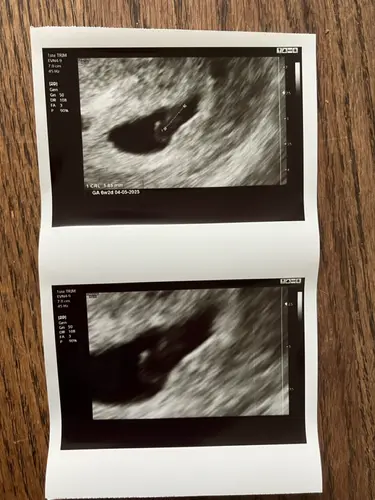

Eerste echo 6w 🥰 dacht zelf 6w5d maar terug gezet waardoor ik nu 1 mei ben ...

Heel gaaf! Was je precies 6 weken? Ik heb met 6+1 of 6+2 een eerste echo (medisch), maar vraag me af of het hartje dan al kan kloppen. Las online 6e week, maja welke dag in de 6e week denk ik dan haha